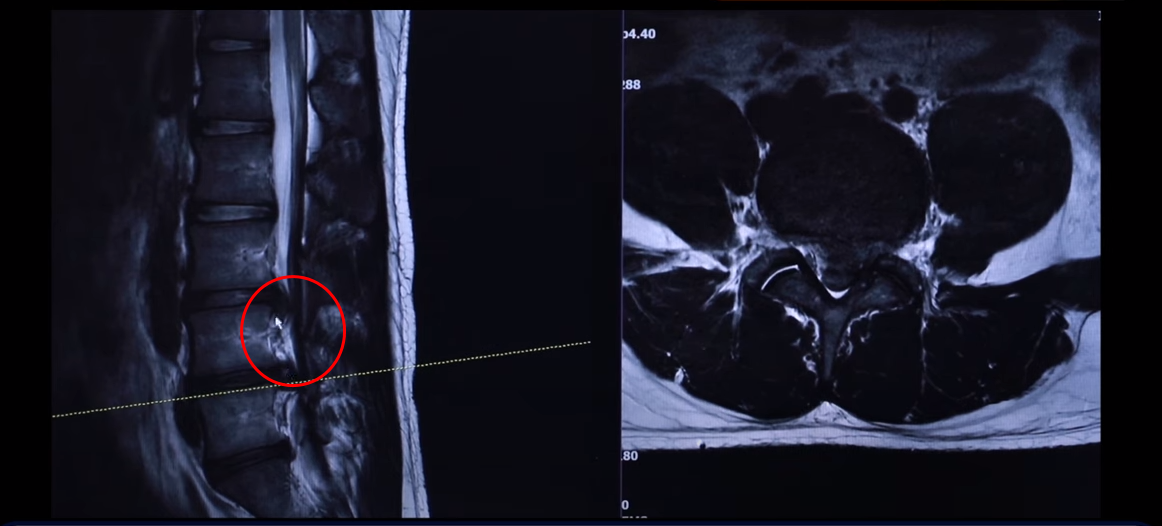

여기 24세 남자 환자분 MRI 보도록 하겠습니다. 옆에서 보는 MRI 보시다시피 어마어마하게 지금 심하게 터져 있습니다. 일반인이 보셔도 아실 정도로 두 마디가 아주 심하게 터졌고 여기도 약간 밀려 나와 있습니다.

단면을 한번 보도록 하겠습니다. 여기를 잘라서 본 단면인데요. 왼쪽으로 많이 밀려 나와 있죠? 이 한마디만 해도 파열돼서 상당히 많이 밀려 나온 겁니다. 왼쪽 다리가 저리고 아플 수 있습니다.

그 다음 마디 4번, 5번 보시면 보시다시피 아예 신경이 거의 보이지 않을 정도로 많이 밀려나왔습니다. 이렇게 심하게 파열된 경우를 보는 건 참 드뭅니다. 거의 신경이 보이지 않을 정도로, 오른쪽에 약간 하얀 부분이 남아 있습니다. 그래서 이 환자분 증상이 왼쪽 다리 증상입니다.